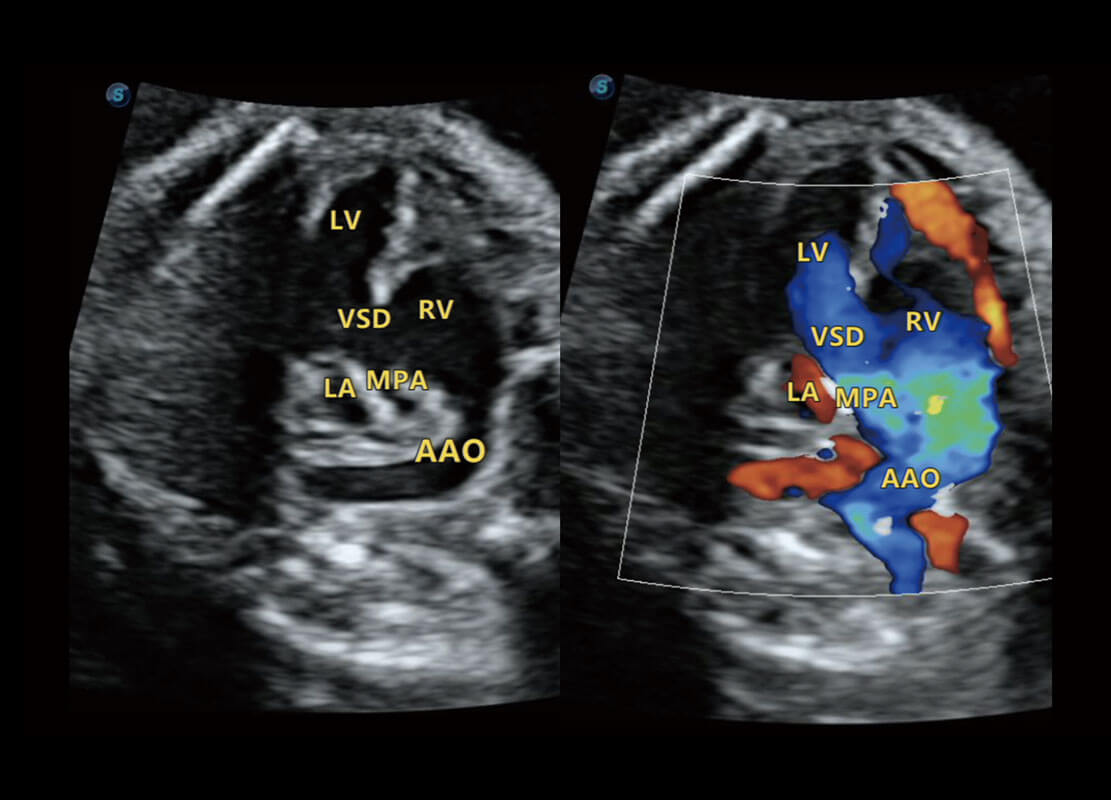

胎心筛查

P60搭载一系列胎儿心脏成像技术,实现更精细的胎儿心脏评估。

• 四腔切面

• 四腔心血流

• 右室双出口

• 胎心容积成像